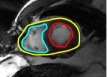

IV-A Tracking Multiple Regions

In cardiac image analysis, there are multiple structures (the right and left ventricles, and myocardium) that all useful and should be segmented. Our method is easily adaptable to this case. Indeed, computation of in Section III-C can be readily generalized. In general, multiple level sets should be used to represent multiple regions. However, in our case of interest (ventricles and surrounding epicardium), the regions form a rather simple topology (see Figure 3), and all regions can be represented using a single level set.